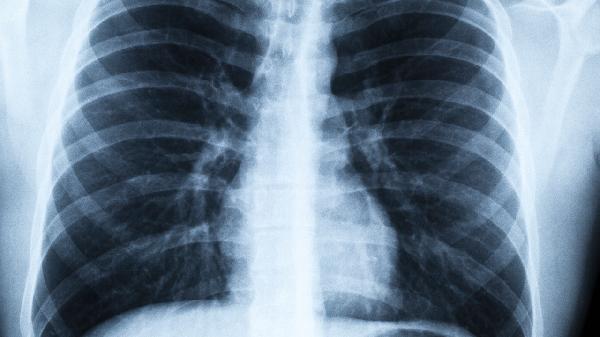

2、警惕睡眠呼吸暂停

约38%的肺气肿患者合并睡眠呼吸暂停综合征。如果夜间频繁憋醒,建议进行专业睡眠监测。